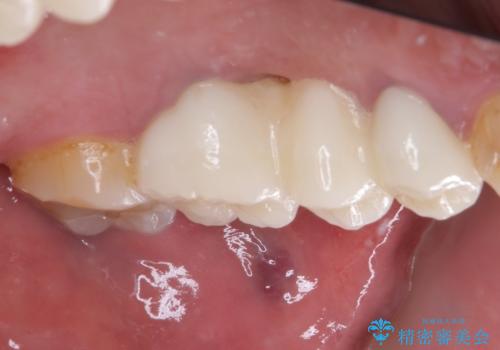

ものが挟まって痛む 割れてしまった歯のオールセラミックブリッジ治療

- 奥歯に物が挟まり、痛みを感じるとのことで来院された患者様です。

レントゲン写真より、歯が破折している可能性が示唆され、歯槽骨が大きく欠損している様子が分かりました。

3歯のクラウンを除去し、破折が疑われる歯をチェックしたところ、予想通り破折していたため、抜去することとしました。

抜歯後、骨吸収量が多く、歯肉のラインが不揃いとなっているため骨造成術を、硬い歯肉が失われて清掃性が低下するため角化歯肉の移植術を行い、また並行して支台歯の根管治療を行っていき、環境を整えた上でオールセラミックブリッジにて補綴治療を行うこととしました。